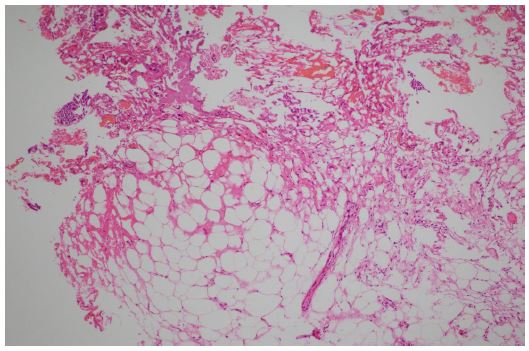

Figure 4: The biopathology examination showed the fibrous fat and a small amount of mucosal tissue. HE 40×.

Figure 5: The biopathology examination showed the fibrous fat and a small amount of mucosal tissue. HE 100×.

The biopathology examination showed the fibrous fat and a small amount of mucosal tissue (Figure 4-5).